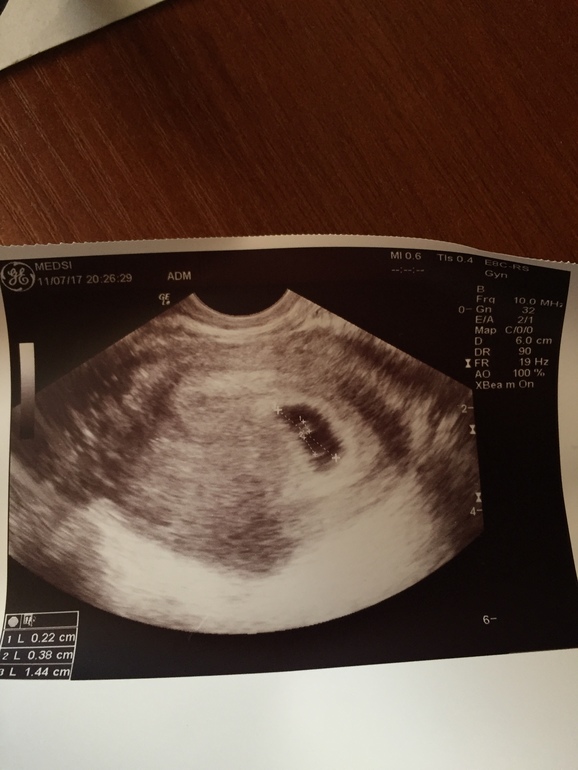

Опустились руки, но надежда умирает последней! Первый день последних месячных был 23.05.17. Половой акт был с 12.06 по 16.06. И вот задержка месячных, делаю тест 26.06.17 заветные две полоски, делаю хгч , он 220. Пришла к врачу, говорит все хорошо, хгч хорошо, но поздняя овуляция была. Думаю ладно, 5 июля ещё сказала хгч сдать, сделала, результат 4980. 11 июля иду опять к врачу, посмотрела (УЗИ прилагаю) , говорит опять все хорошо, виден эмбрион но пока сердцебиения нет, говорит приди 16.07. и сдай ещё раз хгч.13.07 я ещё раз сдаю хгч и он уже 14 145. Пришла сегодня к врачу, говорит эмбриона не видит, сердцебиения нет, какая то аномалия с желточным мешочком , типа как будто их два и какая то дуга... приди говорит во вторник, если это анамалия подтвердится, то на чистку, так как по последним месячным 8 акушерских недель и все должно быть... как так, на прошлом УЗИ все ок, а сейчас анамалия..и хгч говорит Плохо растёт....Девочки, если поздняя овуляция была, то скорее всего в период с 12.06 по 16.06 мы зачали нашу кроху, то это максимум 4 недели от зачатия, а не 6, разве не так? Завтра хочу сходить в другую клинику, что там скажут... может уже я что-то не понимаю, после разговора с врачем совсем поникла...(((((